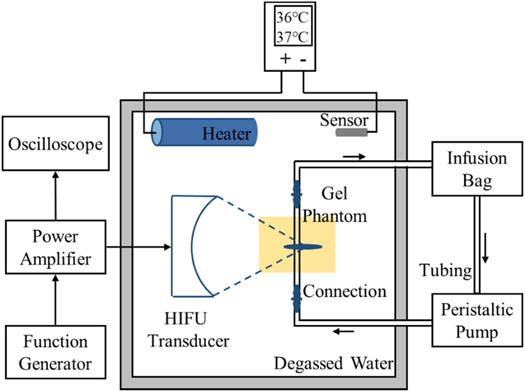

Figure 2. Experimental setup for vascular phantom with HIFU exposure.

The experimental setup is illustrated in figure 2. The spherical transducer (PA885, Precision Acoustics, Dorchester, UK) had an aperture of 60 mm and a radius of curvature of 75 mm. It worked at its third harmonic frequency (3.35 MHz). The lengths of −6 dB focal region were 6.75 mm and 0.75 mm respectively in axial and lateral directions using open-access FOCUS software (McGough RJ 2010). The excitation signal generated by a function generator (33500B, Keysight Technologies, CA, USA) and a power amplifier (1020 L, Electronics & Innovation, NY, USA) was fed to the transducer. An oscilloscope (DSO-X 4024 A, Keysight Technologies, CA, USA) was used to measure the output voltage of the transducer. The transducer and vascular phantom were placed at the fixed positions in the experimental setup. They were immersed in the tank (L × W × H = 32 cm × 25 cm × 15 cm) full of degassed and deionized water.

A heating system was used to maintain the temperature of the degassed water in the range of 36 °C–37 °C in the tank. It consisted of a heater, temperature sensor and controller. The heater and temperature sensor were fully immersed in degassed water when in use. The starting temperature and ending temperature of the temperature controller were set to 36.0 °C and 37.0 °C.